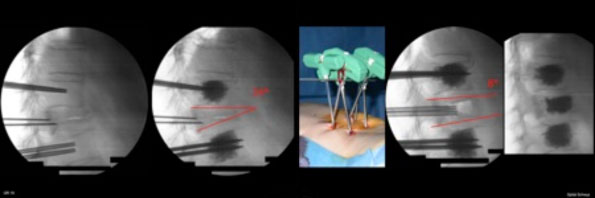

Eine sogenannte Infiltrationsbehandlung kann bei starken Schmerzen den Krankheitsverlauf erheblich verkürzen. Dabei wird eine feine Nadel unter Röntgenkontrolle eingebracht und präzise in die Nähe des zu behandelnden Nervs platziert und ein kristallines Kortison direkt an den Krankheitsort gespritzt. Durch die hohe örtliche Konzentration des sehr stark entzündungshemmenden Kortisons kommt es zur Abschwellung der eingeengten Umgebung und des Nervs selbst. Dies wiederum kann den Heilungsverlauf beschleunigen und rasch zur Schmerzminderung beitragen.

Eine sogenannte Infiltrationsbehandlung kann bei starken Schmerzen den Krankheitsverlauf erheblich verkürzen. Dabei wird eine feine Nadel unter Röntgenkontrolle eingebracht und präzise an den Bandscheibenvorfall respektive an den zu behandelnden Nerv platziert und ein gebundenes Kortison direkt an den Krankheitsort gespritzt. Durch die hohe örtliche Konzentration des sehr stark entzündungshemmenden Kortisons kommt es zur Abschwellung der eingeengten Umgebung und des Nerven selbst. Dies wiederum kann den Heilungsverlauf beschleunigen und rasch zur Schmerzminderung beitragen.

Die Stabilisierungsoperation kann entweder vom Rücken oder vom Bauch erfolgen. In den meisten Fällen wird sie vom Rücken her ausgeführt. Die Rückenmuskulatur wird hierfür seitlich abgeschoben, um einen Zugang zur Wirbelsäule zu ermöglichen. Dann werden 2 Titanschrauben in jeden Wirbelkörper eingeschraubt und mit Längsstangen verbunden. Zusätzlich wird häufig die Bandscheibe ausgeräumt und mit einem Platzhalter einem sogenannten Cage ersetzt. Dieser wird mit eigenem Knochen gefüllt. In seltenen Fällen wird Ersatzknochen oder Fremdknochen dazu gemischt. Der Platzhalter hat die Funktion, dass das Bandscheibenfach offen bleibt und die natürliche Form der Wirbelsäule erhalten bleibt. Gleichzeitig werden unter dem Operationsmikroskop eingeengte Nerven und der Spinalkanal befreit. Die Schrauben und Stäbe haben die Aufgabe, die Wirbelsäule so lange ruhig zu stellen bis der Knochen in den Platzhaltern zu einem Zusammenwachsen der Wirbel geführt hat. Erst dann ist eine dauerhafte Versteifung der Wirbelsäule erreicht. Dieser Vorgang dauert in der Regel 3 Monate. Bei Rauchern ist das Zusammenwachsen stark verlangsamt oder es kann ganz ausbleiben. Eine Metallentfernung ist meist nicht nötig, da das Metall nur selten stört und Titan gut verträglich ist.